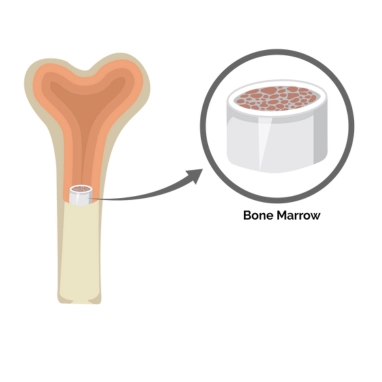

Epidural Hematoma Surgery is performed to remove blood pooled between the skull and the outer layer of the brain, known as the dura mater. This condition usually occurs due to trauma, accidents, or skull fractures and leads to rapid pressure buildup. The surgery prevents brain damage, restores blood flow, and stabilizes the patient. Early intervention is critical for successful recovery.